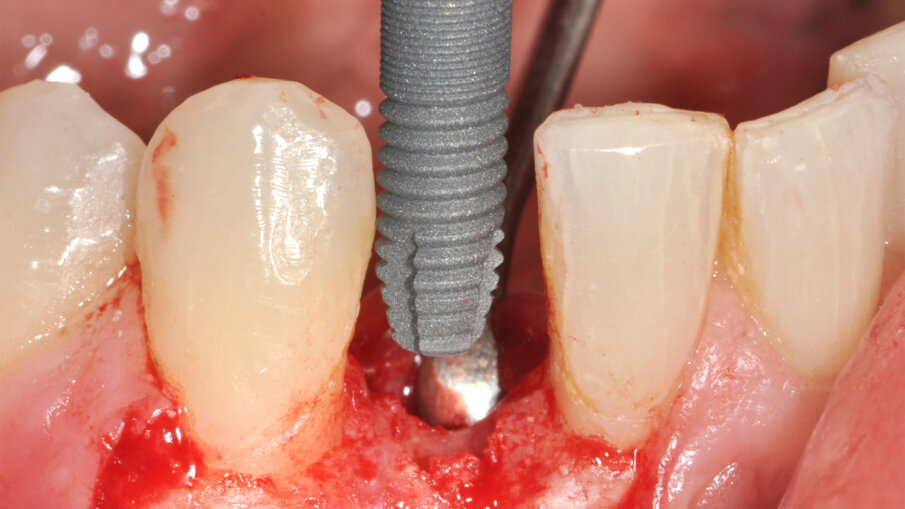

Zavedení implantátu